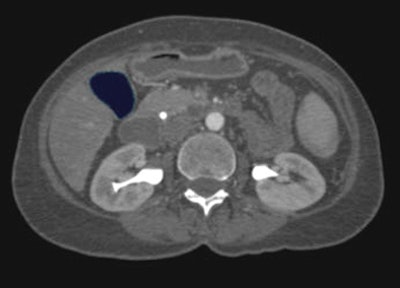

![]() |

| The gallbladder is then removed by executing a simple remove algorithm. |